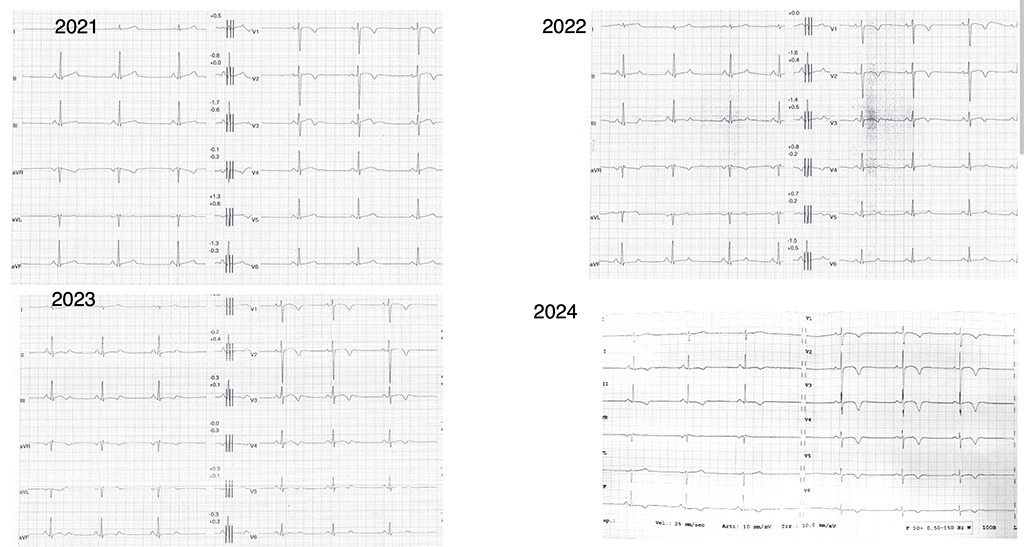

Lo sport diventa rifugio, forza, identità. Poi arriva la corsa in montagna, in solitaria. Giulia non vinceva: dominava. Le avversarie gareggiavano per il secondo posto. Ma qualcosa la spinge a chiedere una valutazione. Non si sentiva bene? L’ECG mostra un pattern familiare: onde T sempre più negative nelle derivazioni antero-laterali, perdita di vettori in V4-V6. Un’evoluzione sospetta (Figura 1). Ne abbiamo già visti, troppi, così. Nel 2023, le prime aritmie ventricolari. Poi tre sincopi da sforzo. La prima durante una gara al sole: si ferma, cade a terra. I test iniziali (Holter, ecocardiogramma) non mostrano nulla. Nessuna seduta di allenamento monitorata. Si continua a valutare atlete ed atleti in modo “statico”: ogni anno fa storia a sé. Nulla di più pericoloso. Le sincopi si ripetono. Dopo l’ultima va in Pronto soccorso. L’ECG è peggiorato, aritmie polimorfe anche a riposo. Finalmente si prescrive una risonanza magnetica con contrasto. Ma è negativa. Non ci convince. La ripetiamo: il quadro è devastante. Ventricolo sinistro moderatamente dilatato, funzione sistolica lievemente ridotta, parete laterale assottigliata e ipocinetica. Anche il ventricolo destro presenta una focale acinesia. E ovunque, un bianco che non consola come la neve che Giulia è abituata a vedere durante le sue salite invernali. È un bianco che spaventa, è il bianco del gadolinio che si accumula a disegnare la malattia. Diagnosi: cardiomiopatia aritmogena biventricolare. L’ECG non mentiva. Rivedendo la prima risonanza, scopriamo che il quadro era già presente.